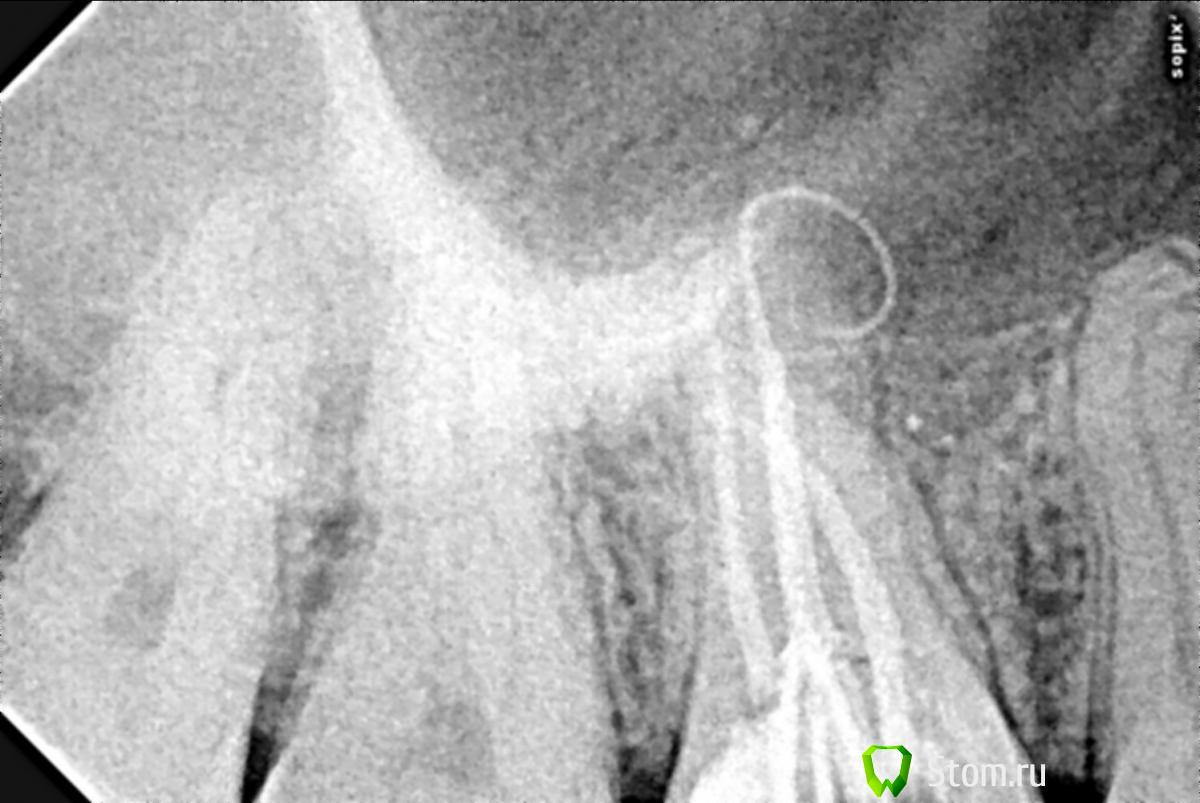

spfrld Опубликовано 7 марта, 2012 Поделиться Опубликовано 7 марта, 2012 Добрый день, проблема в следующем. При пломбировке канала, гуттаперча была выведена за верхушку канала. Первые 3-4 дня сохранялись болевые ощущения при накусывании. По прошествии недели болезненных ощущений не наблюдается. Вопрос: оставить как есть или удалить хирургическим путем? Заранее спасибо! Ссылка на комментарий

spfrld Опубликовано 9 марта, 2012 Автор Поделиться Опубликовано 9 марта, 2012 Спасибо всем за участие. Еще небольшой вопрос: не усматривается ли по снимку попадание штифта в гайморову пазуху? Ссылка на комментарий

ger_berra Опубликовано 9 марта, 2012 Поделиться Опубликовано 9 марта, 2012 это невозможно определить со 100% увереностью.Рг-снимок-это двухмерное изображение трехмерного объекта. Ссылка на комментарий